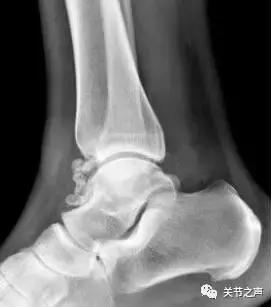

除了肩关节,髋、膝、踝、肘、腕几乎全身各个关节都有可能长珍珠。

重要提示:关节腔游离体一旦发现,要尽早取出。

若等到疼痛症状非常严重、卡压交锁非常频繁时,关节内软骨大多已经磨损得非常严重了,继发造成的创伤性关节炎不可逆转。